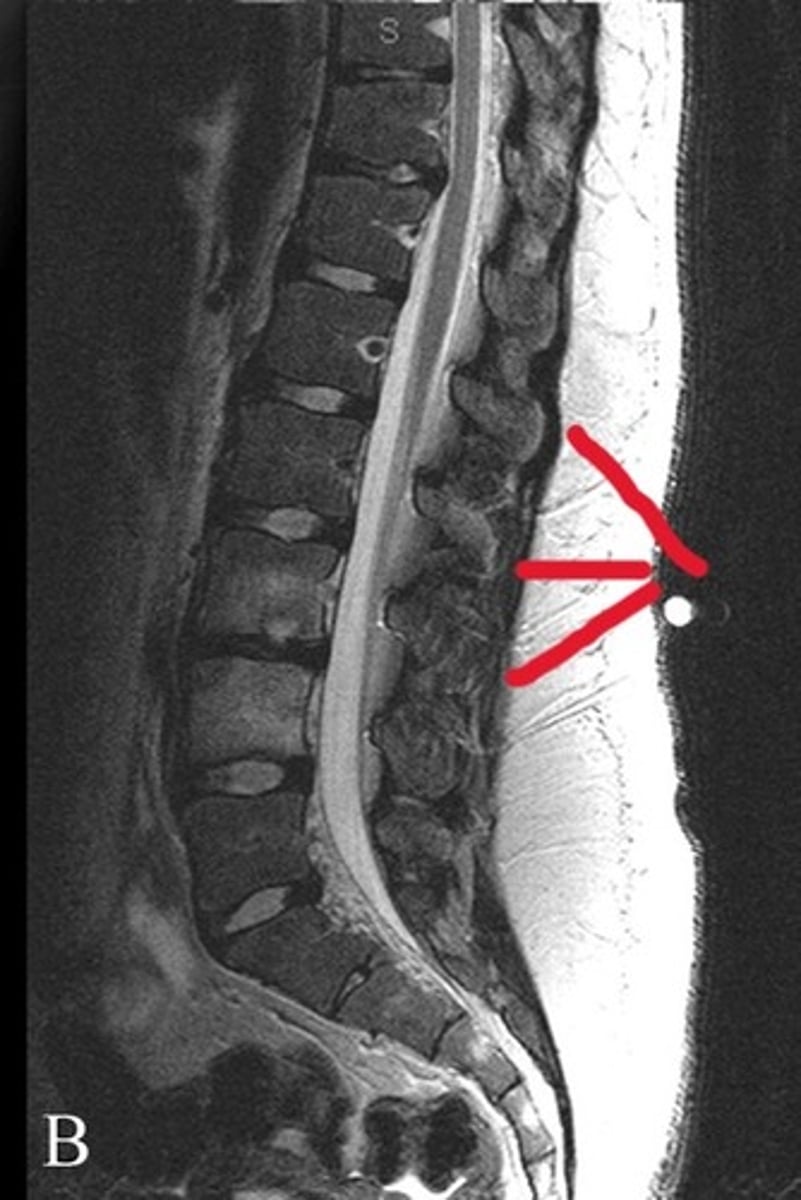

Spinous processes

What structures are these lines pointing to

Blue line- vertebral bodies

Red line- spinal canal

What is the blue line pointing to and what is the red line pointing to

False- pathology spotted on the thoracic spine

T or F: This is normal anatomy